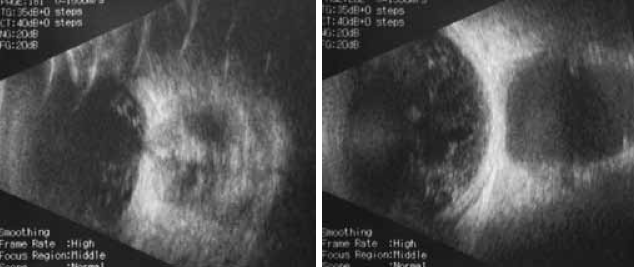

Кроме того, в ходе эхобиометрии глазного яблока выявлены деструкция стекловидного тела и колобома зрительного нерва (рис. 2).

Рис. 2. Деструкция стекловидного тела и колобома зрительного нерва левого глаза ребенка А. (сонограмма)

При ультразвуковом сканировании подтверждено смещение правого глазного яблока кпереди, выявлена его деформация в заднем полюсе. Ретробульбарно лоцировалось полостное образование, заполненное гомогенной жидкостью, оболочки которого по толщине соответствуют толщине склеры.